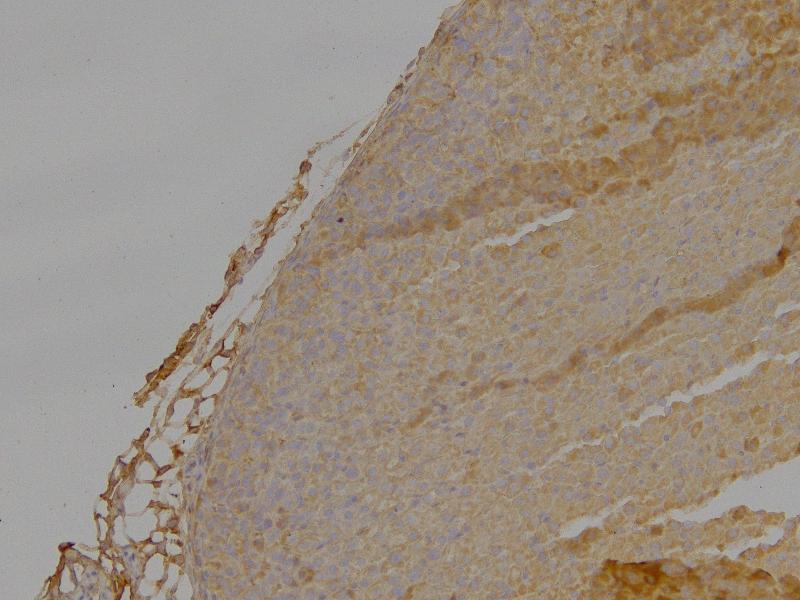

Immunohistochemistry: Paraffin embedded Mouse Adrenal Gland. Recommended concentration: 4 μg/mL.